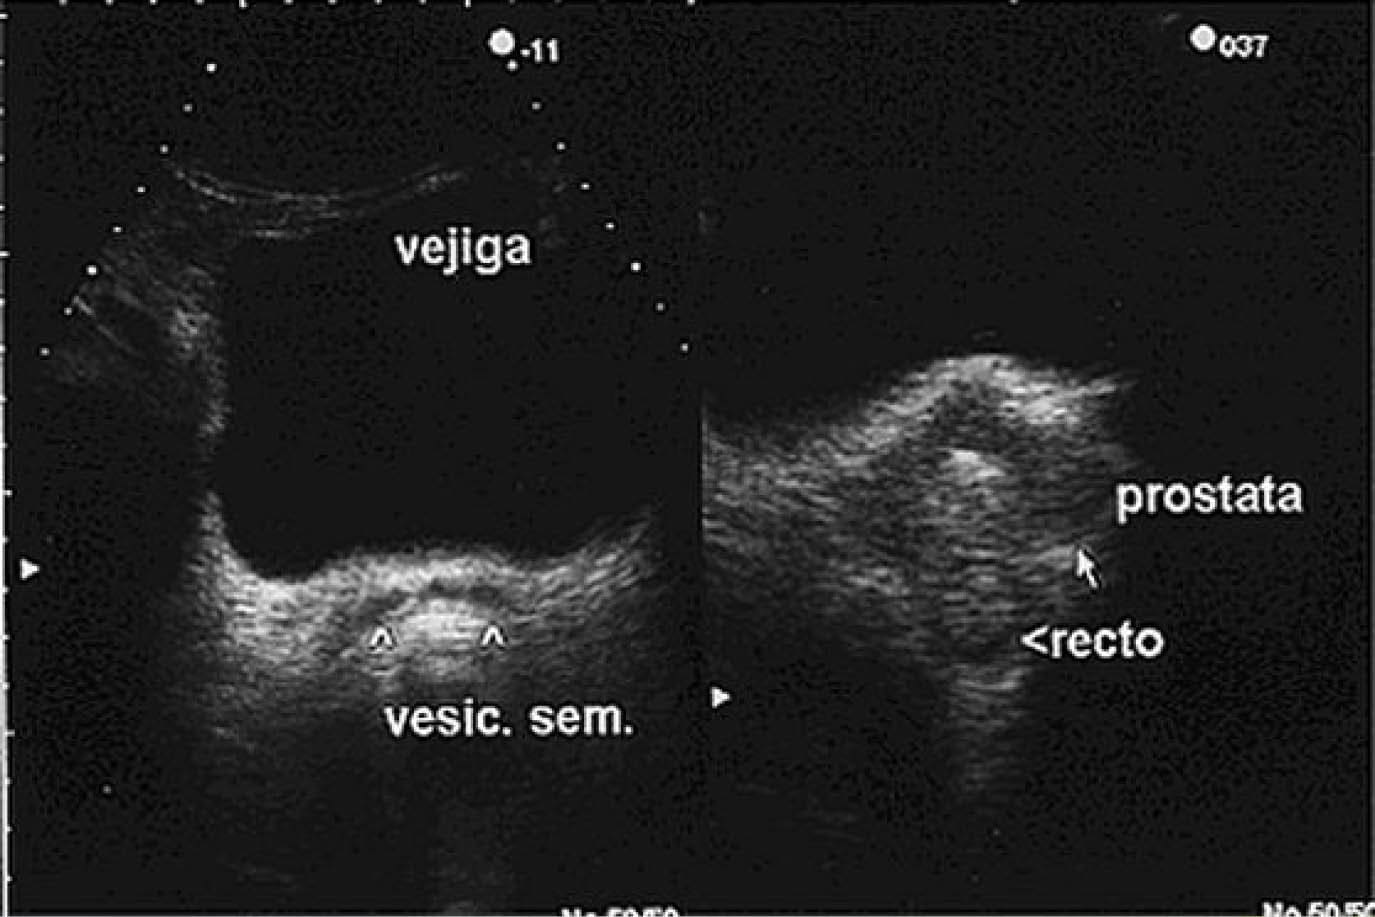

Existen varios métodos para realizar una prostatectomía, y la elección del método depende de varios factores, incluyendo la etapa y la gravedad del cáncer de próstata, la salud general del paciente y la experiencia del cirujano. Algunos de los métodos más comunes para realizar una prostatectomía son:

• Prostatectomía radical abierta: En este procedimiento, se realiza una incisión en el abdomen o en el área entre el escroto y el ano (incisión perineal) para acceder a la próstata y extirparla. Esta técnica permite al cirujano una visión directa y completa de la próstata y las estructuras circundantes.

• Prostatectomía radical laparoscópica: En este método, se realizan varias incisiones pequeñas en el abdomen a través de las cuales se insertan instrumentos quirúrgicos y una cámara. El cirujano realiza la operación utilizando imágenes ampliadas en un monitor. Esta técnica suele resultar en una recuperación más rápida y menos dolorosa que la prostatectomía abierta.

• Prostatectomía radical asistida por robot (prostatectomía robótica): Este método es similar a la laparoscopia, pero se utiliza un sistema robótico controlado por el cirujano para realizar la operación. Los brazos robóticos proporcionan movimientos más precisos y una mayor capacidad de maniobra, lo que puede mejorar la precisión y reducir el riesgo de daño a los tejidos circundantes.

• Prostatectomía transuretral: Este procedimiento se utiliza principalmente para tratar la hiperplasia prostática benigna (HPB) y consiste en extirpar la parte interna de la próstata a través de la uretra utilizando un instrumento llamado resectoscopio. Aunque es menos invasivo que otros tipos de prostatectomía, generalmente no se recomienda para tratar el cáncer de próstata, ya que no puede extirpar por completo el tejido canceroso.